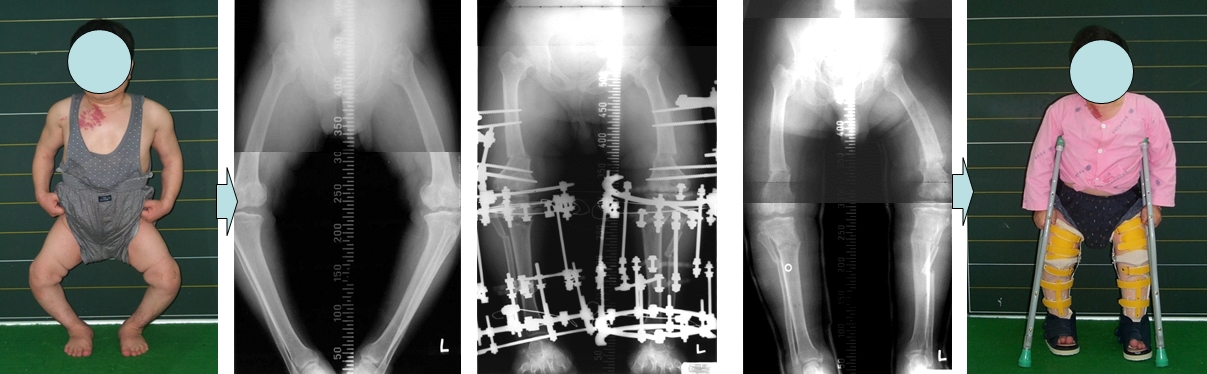

공지 가성연골무형성증환자의 하지변형에 대한 교정관리자-가성연골무형성증으로 다리가 휘어진 환자가 일리자로프로 교정을 받았습니다. Perform ilizarov technique to treat twisted legs caused by pseudoachondroplasia.다음글공지 다발성골단이형성증환자의 하지변형에 대한 교정 1이전글공지 연골무형성증환자의 하지변형에 대한 교정목록